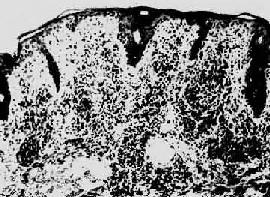

第二期梅毒第一期梅毒如不治疗,即使下疳愈合,潜伏于体内的螺旋体仍能继续繁殖,在感染后第8~10周左右大量进入血循环,引起全身广泛性皮肤粘膜病变,即梅毒疹(syphilid)。通常表现为口腔粘膜红斑、丘疹、躯干、四肢、掌心和足心的斑疹、丘疹和口唇、外阴、肛周的扁平湿(condyloma lata)。后者表现为暗红色突起的平坦斑块。所有梅毒疹的组织学变化皆为淋巴细胞和浆细胞浸润构成的非特异性炎及闭塞性血管内膜炎和血管周围炎(图18-26),扁平湿则尚有表皮增生和角化不全。凡梅毒疹病灶内皆有苍白螺旋体。第二期梅毒有全身性淋巴结肿大,镜下为非特异性炎。少数患者可发生亚急性脑膜炎、虹膜炎或肝炎,以及免疫复合物反应所引起的膜性肾小球肾炎。梅毒疹也可不治“自愈”,但患者实际陷入隐性梅毒阶段,若不治疗,多年后30%的患者将发生第三期或晚期梅毒。第二期梅毒若予治疗,将阻止其向第三期梅毒发展。

图18-26 梅毒

真皮呈致密的淋巴细胞及浆细胞浸润(采自Muir)